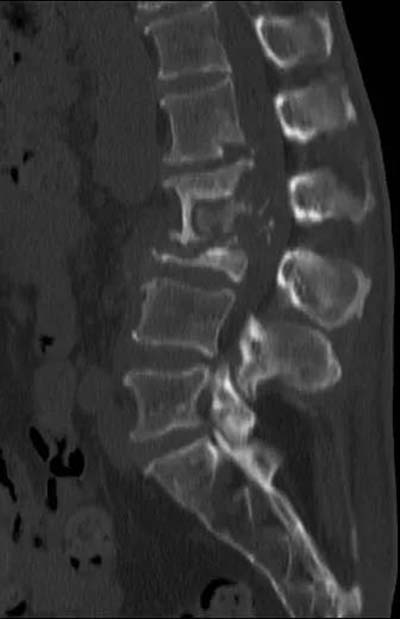

典型的腰椎结核CT影像是:骨质破坏,椎间隙消失,

死骨形成,塌陷,后凸畸形形成。

患者腰背部有骨性后凸,出现成角畸形